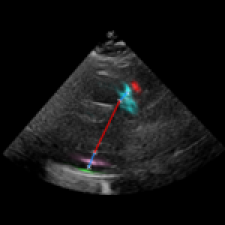

Left Ventricular Hypertrophy (LVH), one of the leading predictors of adverse cardiovascular outcomes, is the condition where heart’s mass abnormally increases secondary to anatomical changes in the Left Ventricle (LV) [10]. These anatomical changes include an increase in the septal and LV wall thickness, and the enlargement of the LV chamber. More specifically, Inter-Ventricular Septal (IVS), LV Posterior Wall (LVPW) and LV Internal Diameter (LVID) are assessed to investigate LVH and the risk of heart failure [21]. As shown in Figure 1 (a), four landmarks on a parasternal long axis (PLAX) echo frame can characterize IVS, LVPW and LVID, and allow cardiac function assessment. To automate this, machine learning-based (ML) landmark detection methods have gained traction.

It is difficult for such ML models to achieve high accuracy due to the sparsity of positive training signals (four or six) pertaining to the correct pixel locations. In an attempt to address this, previous works use 2D Gaussian distributions to smooth the ground truth landmarks of the LV [9, 13, 18]. However, as shown in Figure 1 (b), for LV landmark detection where landmarks are located at the wall boundaries (as illustrated by the dashed line), we argue that an isotropic Gaussian label smoothing approach confuses the model by being agnostic to the structural information of the echo frame and penalizing the model similarly whether the predictions are perpendicular or along the LV walls.